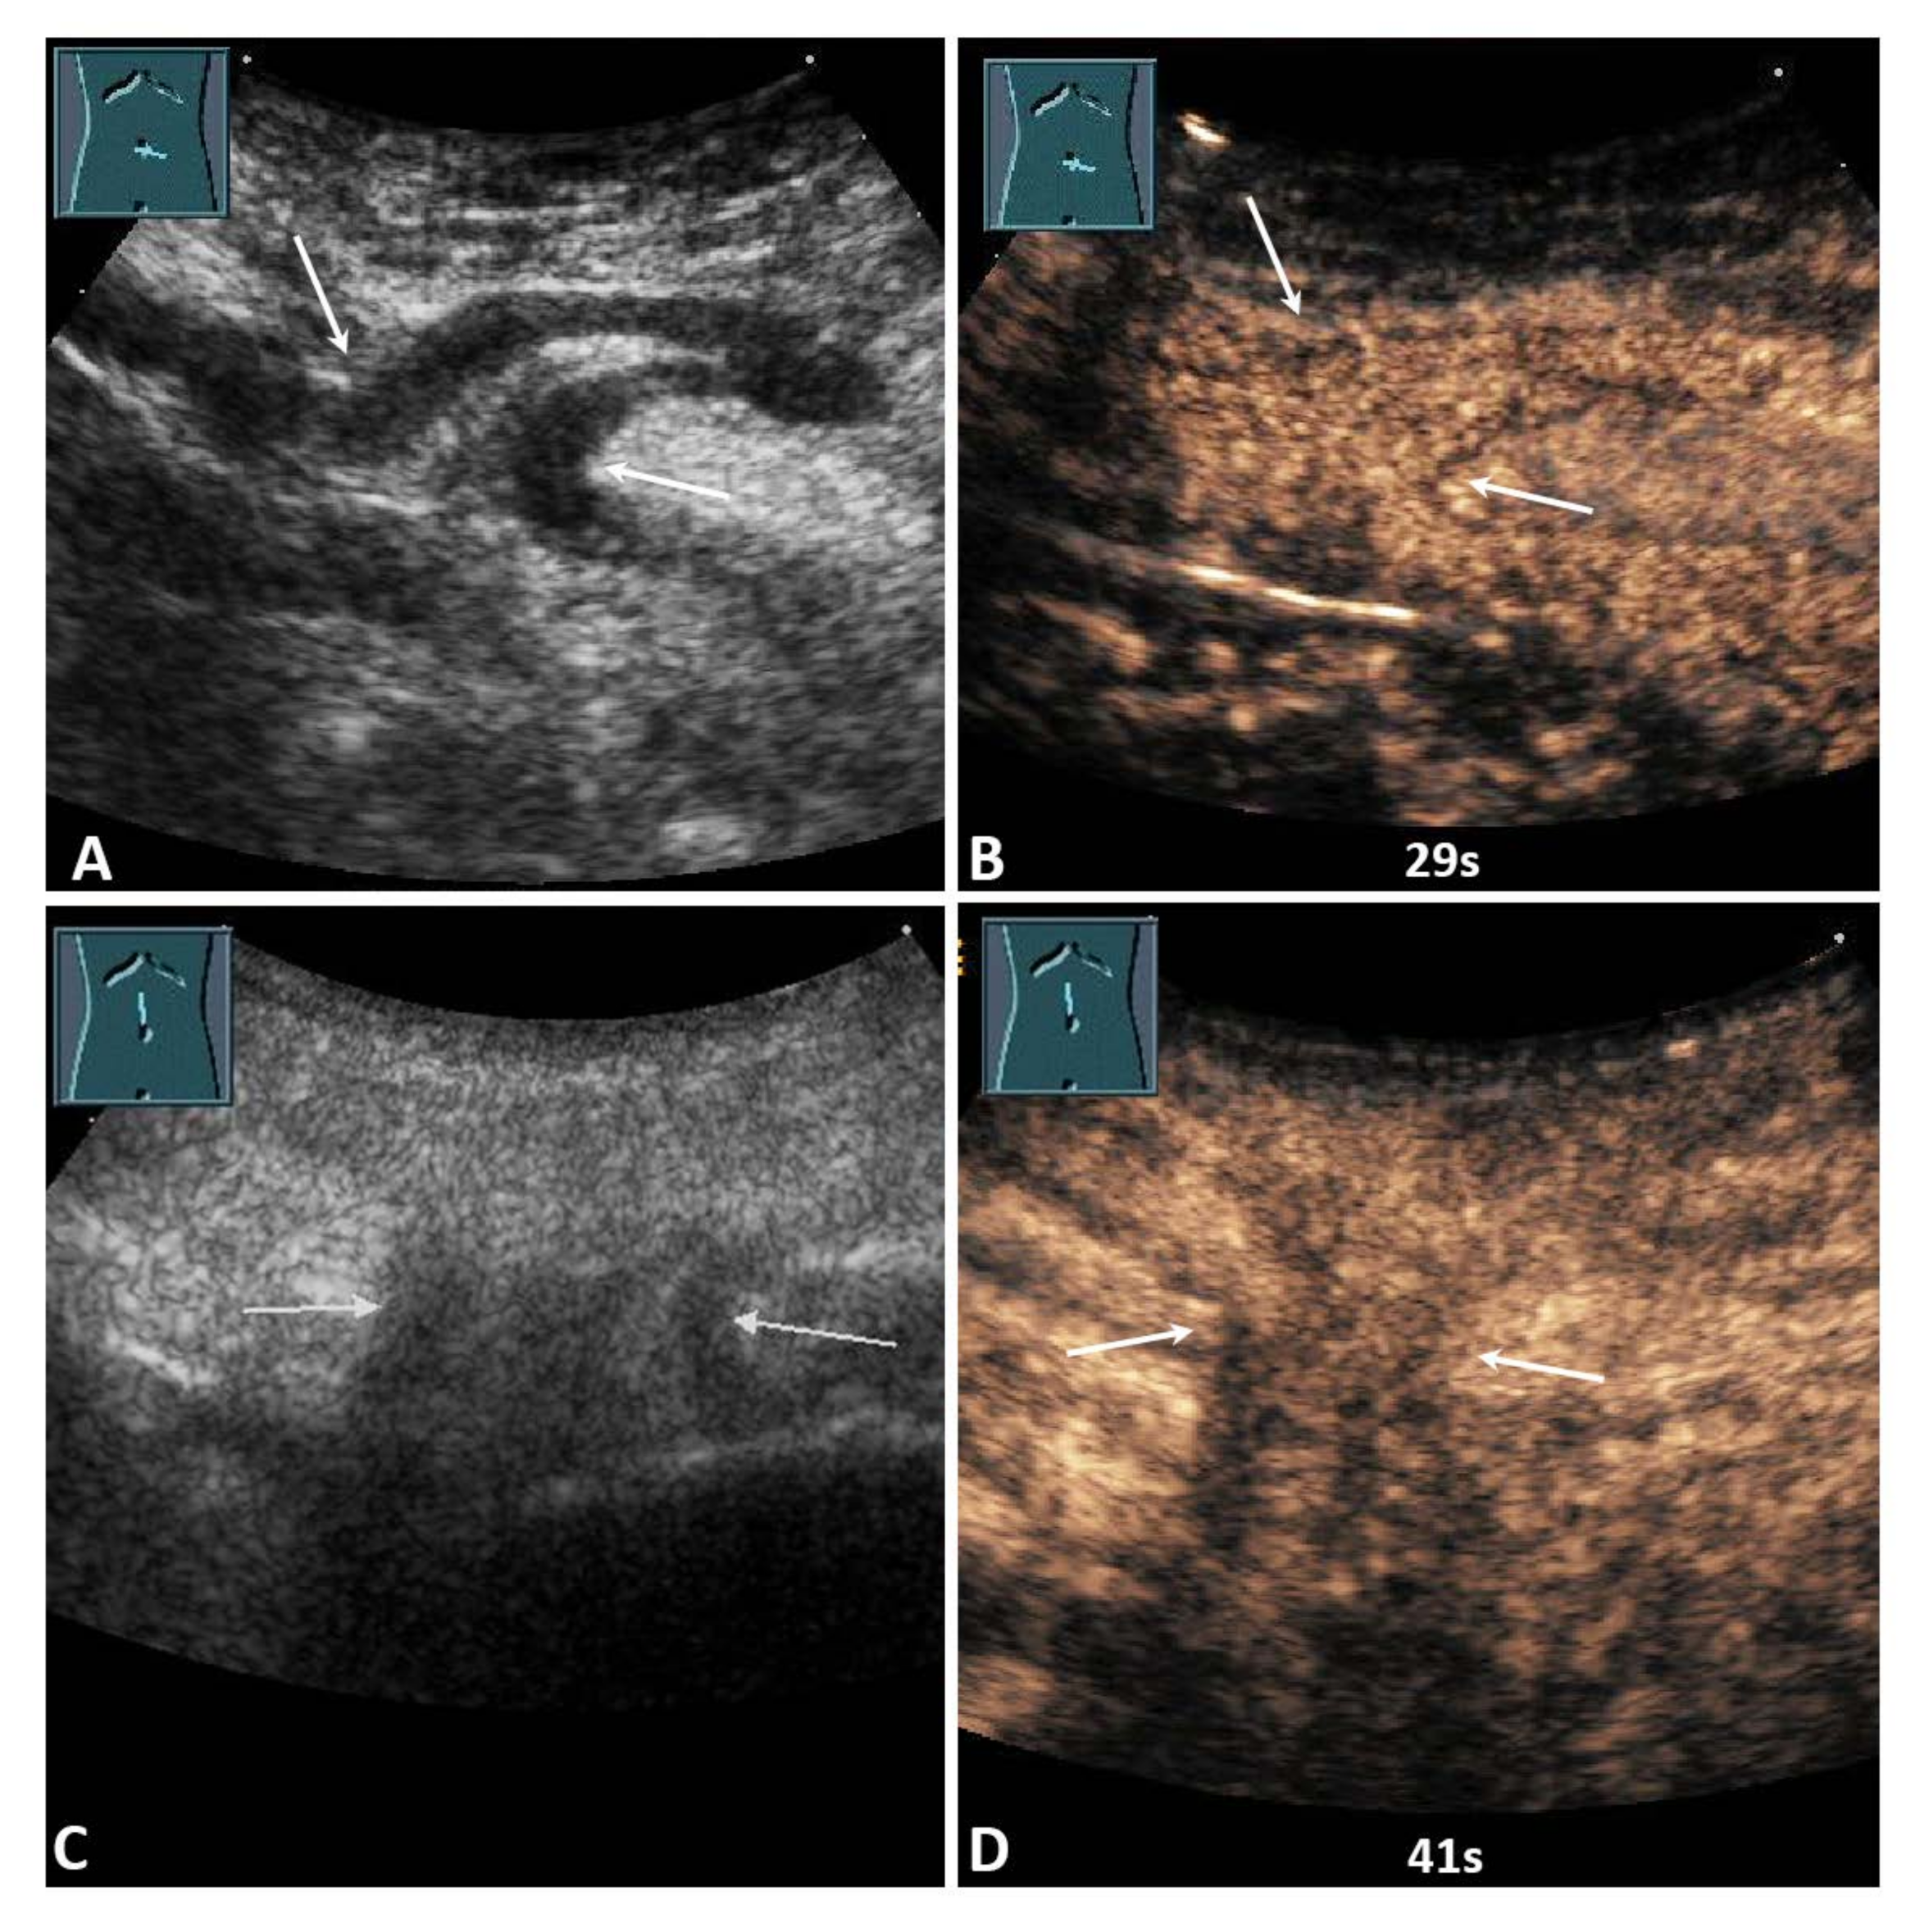

Figure 5.

(A) A 59-year-old male patient with acute pain in the paraumbilical region. B-mode ultrasound shows a hernia orifice (arrows), and the hernia sac shows a fixed bowel structure. (B) On contrast-enhanced ultrasound, the loop of small bowel shows a marked enhancement after 29 s. Surgical evaluation showed no evidence of infarction. No resection of the bowel was performed. (C) A 91-year-old female patient with acute pain in the epigastric region. B-mode ultrasound shows a hernia orifice (arrows), and the hernia sac shows fixed omental tissue. (D) On contrast-enhanced ultrasound, the hernia contents show a marked enhancement after 41 s. Surgical evaluation showed no evidence of infarction. No resection of the omentum was performed.